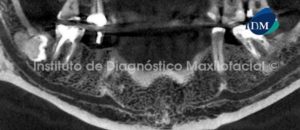

Paciente de sexo femenino y de 59 años de edad es referida al Instituto de Diagnóstico Maxilofacial para realizar el estudio de evaluación ósea para la colocación de implantes, lo cual llamo nuestra atención la presencia de un hallazgo radiográfico en el maxilar inferior.